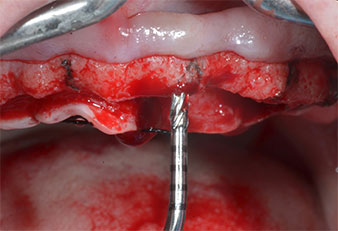

Пиезоелектрически инструмент с диамантено покритие с форма на пламък (Piezomed I1) e използван за маркиране на позициите на имплантите и за пилотна подготовка (Фиг. 3). Препарацията беше извършена с внимателни вертикални движения, с намалена мощност, пълна иригация и лек натиск (под 300 g) След това се приложи пилотен инструмент (Piezomed I2A/ I2P) за първоначално увеличение на диаметъра на имплантното ложе с 2 mm (Фиг. 4), последвано от 3 mm разширение (Фиг. 5)

Ултразву��ов пилотен накрайник за Piezomed

Фиг. 3 Препарацията с ултразвуков пилотен накрайник I1 се извършва с движение нагоре-надолу, успоредно с дългата ос на работната част.